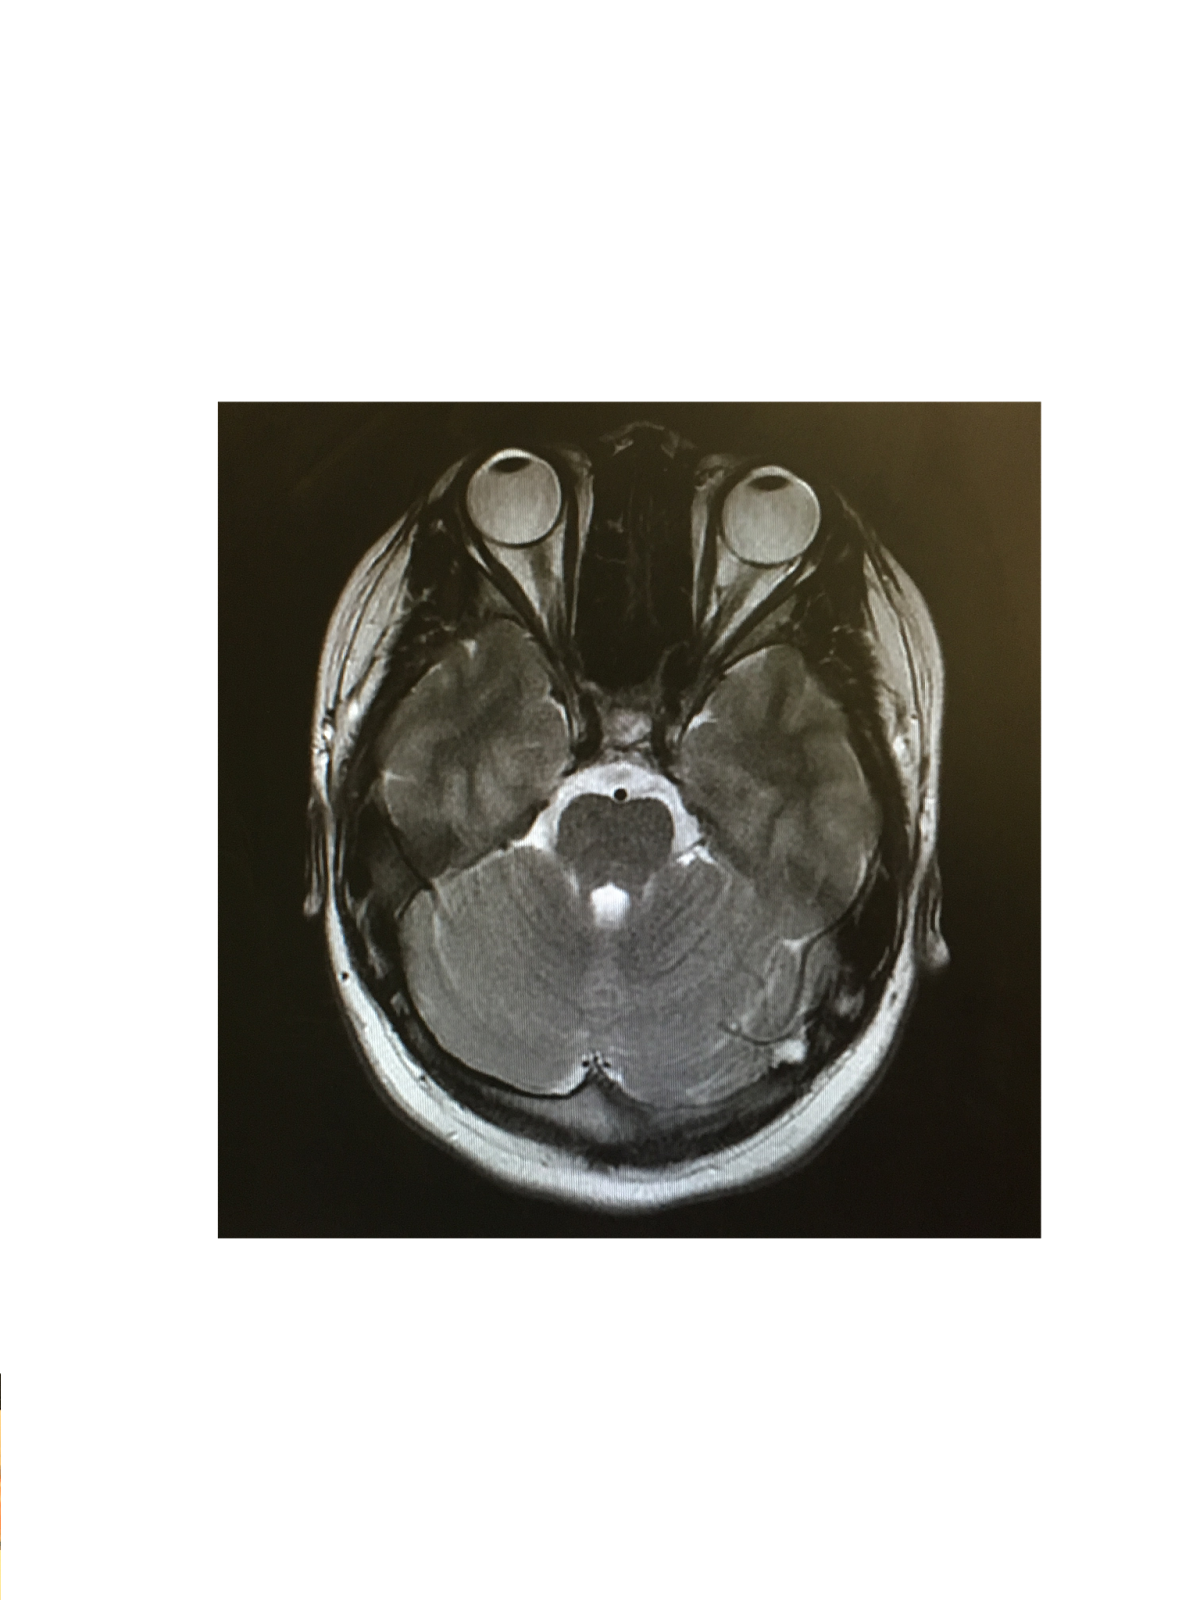

From myjourneywithcushingsdisease.blogspot.com

Fixing The Fat Girl's Future My Journey with Cushing's Disease MRI Cushing's Disease Mri — ct or mri scans can take pictures of the pituitary and adrenal glands to see if anything shows up, such as tumors. 2 mr imaging of the. — cushing disease (cd) is associated with reduced quality of life 1 and excess mortality. The sensitivity of mr imaging in cushing disease is not known. — the sensitivity. Cushing's Disease Mri.